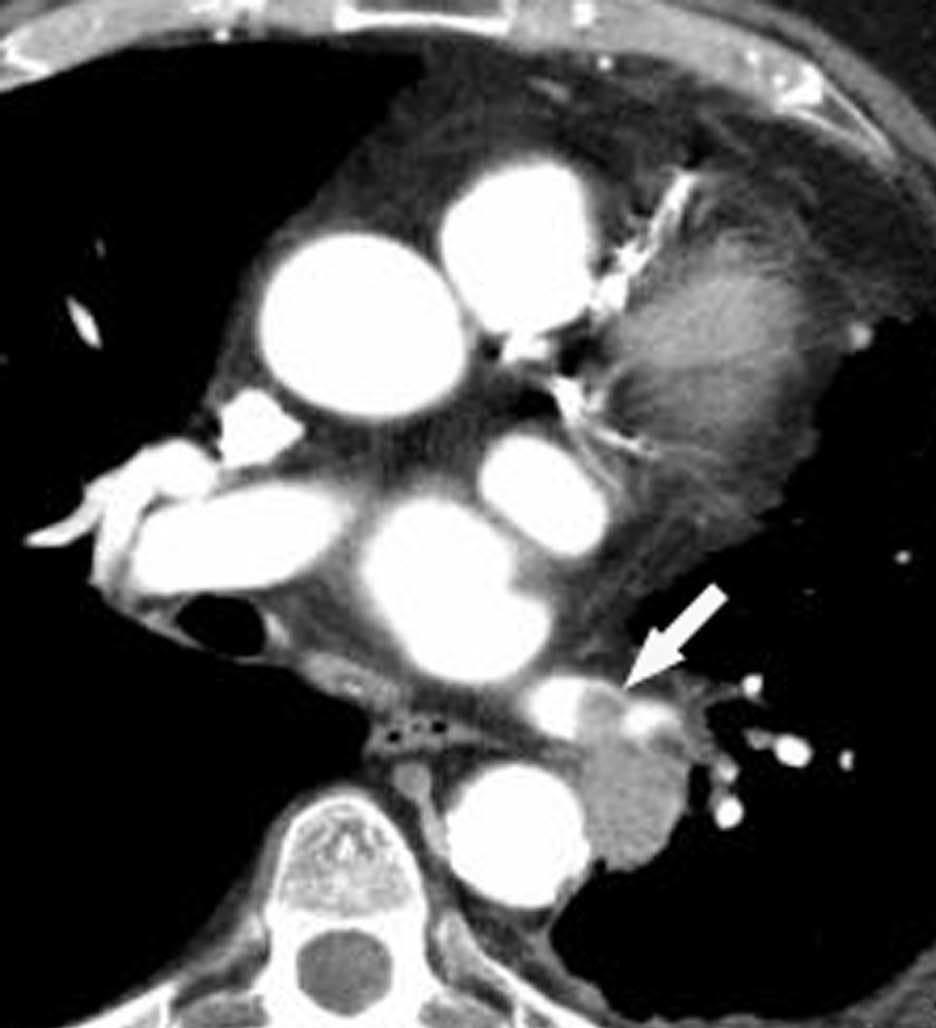

Una ventaja adicional de la TCMC es la capacidad de realizar, como parte del estudio de extensión, una angiografía TC (angioTC) en los tumores de localización central candidatos a cirugía y, fundamentalmente, en aquellos pacientes con hemoptisis que podrían ser subsidiarios de embolización terapéutica. El estudio vascular permite tener un excelente mapa para la cirugía, que ayuda enormemente al cirujano a la hora de planificar la intervención (fig 8). En los pacientes con hemoptisis amenazante, la demostración de una arteria sistémica hipertrófica sirve de guía para la arteriografía y subsecuente terapia endovascular (fig. 9).

Fig. 9.--Hemoptisis masiva secundaria a neoplasia de pulmón. (A) Corte axial con contraste que muestra el origen de la arteria bronquial derecha en la aorta descendente. (B) Reconstrucción de volumen en la que se pone de manifiesto la localización exacta de la arteria bronquial derecha hipertrófica y su exquisita correlación con la angiografía selectiva (C).